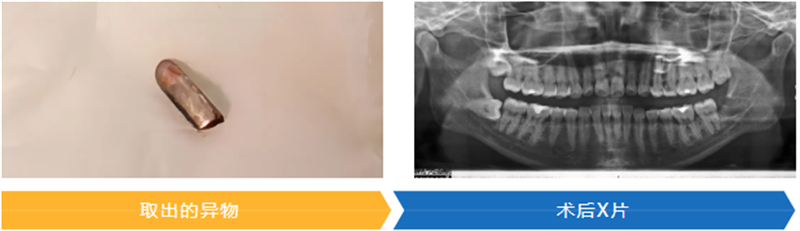

最終,團隊?wèi){借豐富的臨床經(jīng)驗和默契配合,成功將一枚拔牙挺的斷端取出。術(shù)后患者生命體征平穩(wěn),疼痛癥狀明顯緩解,經(jīng)影像檢查確認異物完整取出,目前已進入康復(fù)觀察階段。